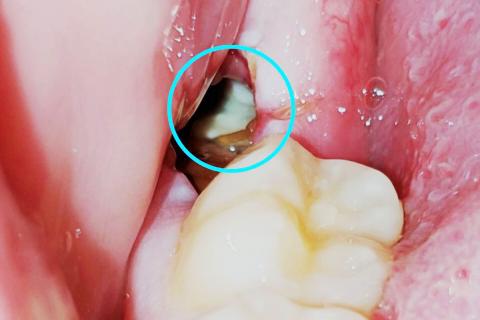

Dry socket (alveolar osteitis)

Dry Socket (Alveolar Osteitis) Analysis and Action Plan

This analysis is based on the visual evidence in the image (which appears to show an exposed socket) and standard dental protocols for Alveolar Osteitis. Note: This is an analysis by an AI and is not a substitute for an in-person examination and diagnosis by a licensed dentist.